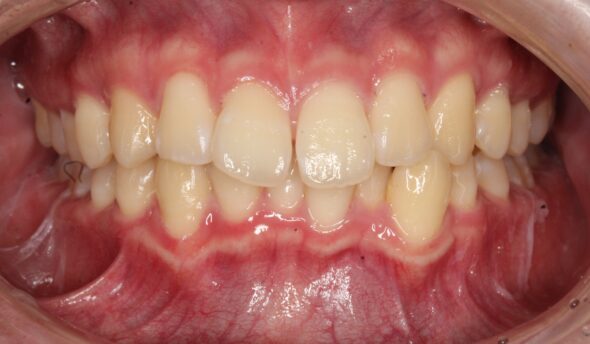

術後:正面

術後:前歯部